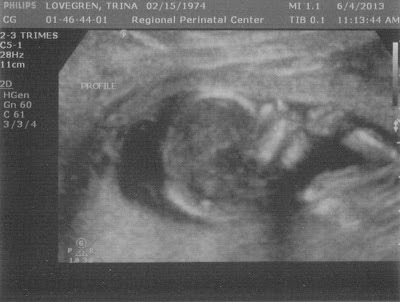

6/4 Genetic testing with Sacred Heart Health. To be honest this appointment was joke to me. First I was given the incorrect address and by the time I got to the correct address and checked in it was exactly my appointment time. I then found out they never sent me any of the required paperwork, so I hurried and completed it and turned it back in 10 minutes after my appointment was to start. 20 minutes later I was called back just to 'check me in' which took 20 minutes. The 'check in' process was having a front office person take my weight, escort me to a room where a nurse was waiting, to be asked the exact same info that I had just filled out while she put it on another piece of paper! She then took my pulse and blood pressure and verified I had left a urine sample. To me all of this seemed excessive just to do a detailed ultrasound for genetic testing, but heck it's their office and protocol, so who am I to complain about their process. I was then escorted back to the waiting room, but was told I should be called back immediately because my appointment was before all the other ladies in the waiting room. Boy was she wrong, another 30 minutes and everyone but the 11am appointment was called back, seen and half of them left before I was called back.

The ultrasound tech explained how she would take measurements and then the doctor would come in to discuss the results and discuss any options for genetic testing, IF I wanted to do genetic testing. HUH????? This is the whole reason why I am here!!! She was just as confused as I was, so she talked about amnio (which we already ruled out) and having me come back in a week or two for a blood draw (which I am already doing next week at my doctors office). I explained to her that the only reason why I was here was for a genetic screening. She understood and got started on the ultrasound. I have to say she was one of the better techs I recall ever having, she let us ask questions and even though she wasn't supposed to tell us anything, she gave us some info. Little turkey looked a bit cramped already and seemed to enjoy having his (no we don't know the sex - we tried, but I think its a boy) hands in front of his face, he never did put them in his mouth and the entire time he was in an Indian style sitting position (even though he was on his back), hence why we couldn't verify the sex. We did find out that 'little turkey' weighs 4 ounces with a heart beat of 140 per minute.

The doctor came in after she completed the ultrasound and did his rant about genetic testing (again the only reason why we are here) and stated that everything appears to be perfect, but wanted us to come back in a month or so to do an anatomy ultrasound, which we are doing at my OB between 18-20 weeks. I currently don't have this scheduled as we are working on all the kids schedules to ensure they can all be at that appoinment! But even after I explained I was already having this done with my regular OB, he went ahead and scheduled me an appointment. UGHHHH! So besides the extreme lack of communication and reason for my appointment, I also realized that my high def ultrasound I was supposed to have today was done on a regular ultrasound machine, my 45 minute appointment turned into a two hour appointment, and this possibly unnecessary ultrasound will cost us a pretty penny! But on the positive side, we got two new pics of our little turkey and Eric lost 3 hours of work time (okay that was a bit sarcastic!).

![]() |

| 14 weeks 5 days |